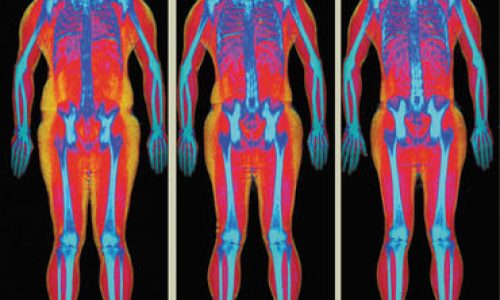

Con tale apparecchiatura, è possibile effettuare la valutazione della composizione corporea fornendo la percentuale di massa grassa, massa magra totale e densità ossea.